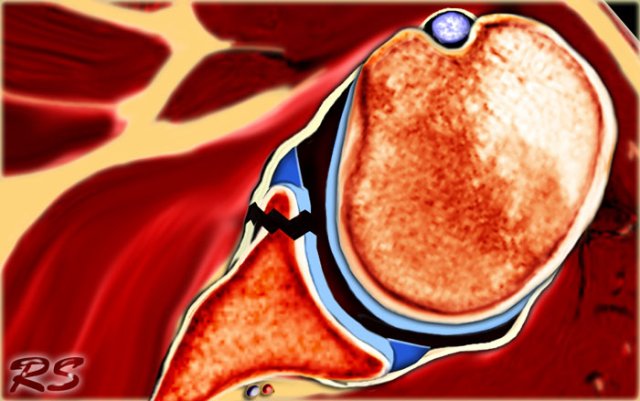

Anterior dislocation

The shoulder almost always dislocates to anterior and inferior, because motion to superior is limited by the acromion, coracoid process and rotator cuff (figure).

Motion in a posterior direction is limited by the posterior rim of the glenoid which is in an anteverted position.

An uncommon cause of anterior dislocation is inpatients with a dysplasia of the glenoid.

The dislocation of the humeral head to antero-inferior causes damage to the antero-inferior rim of the glenoid in the 3 - 6 o'clock position (marked in red).

Especially in younger patients this results in a Bankart fracture or a Bankart lesion which is a tear of the anteroinferior labrum.

This results in instability and recurrent dislocations.

Due to these recurrent dislocations significant bone loss and erosion of the anterior glenoid rim may occur, which maintains the unstable situation.